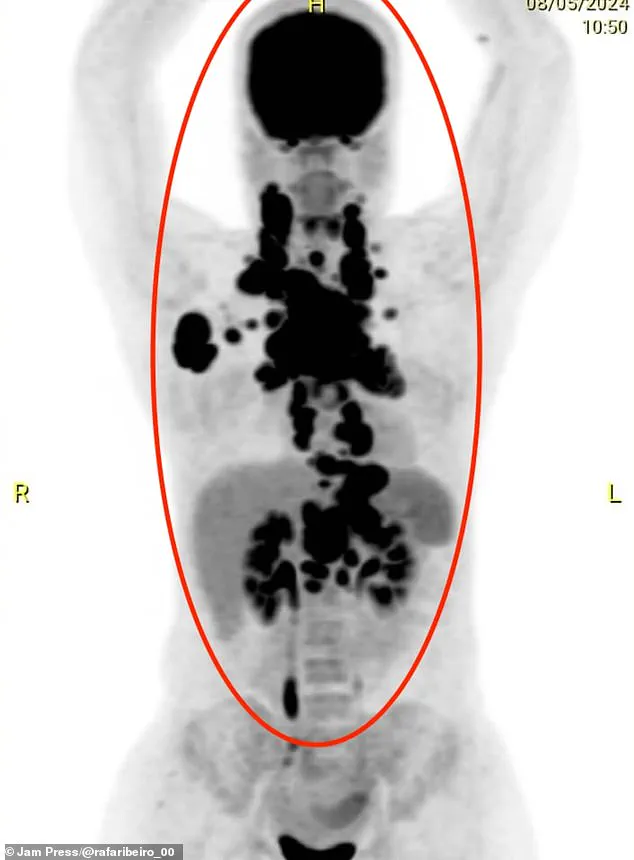

At first, medics dismissed Ms Ribeiro's symptoms as pneumonia or an allergic cough, but after she collapsed and could no longer eat, scans revealed that her upper body was packed full of tumours.

She said: 'The tumours were crushing me from the inside.

My oesophagus was compressed, and my heart felt like it was being taken over, but it was just the pressure from the tumours.' Ms Ribiero began chemotherapy, but during treatment contracted a deadly hospital superbug.

This x-ray shows how tumours were 'crushing' her internal organs.